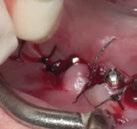

Exploración Intraoral

Presenta un estado oral deficitario. Parcialmente edéntula, con colapso de mordida, migración dental patológica, restauraciones de resina antiguas fisuradas y filtradas, transparencia y exposición de cámara pulpar secundaria a desgastes con pérdida de estructura e integridad de tejido dental importante (Figuras 1 a 4). Portadora a tiempo parcial de prótesis removibles desadaptadas de más de 10 años de antigüedad, refiriendo incapacidad de adaptación a este tipo de prótesis.

Figura 3. Visión intraoral oclusal mandibular. Figura 4. Visión intraoral frontal. Figura 1. Visión intraoral oclusal maxilar. Figura 2. Visión lateral izquierda intraoral. Figura 7. Escaneado intraoral maxilar con Dexis IS3700. Figura 8. Escaneado intraoral mandibular con Dexis IS3700. Figura 5. Visión extraoral lateral sonrisa.